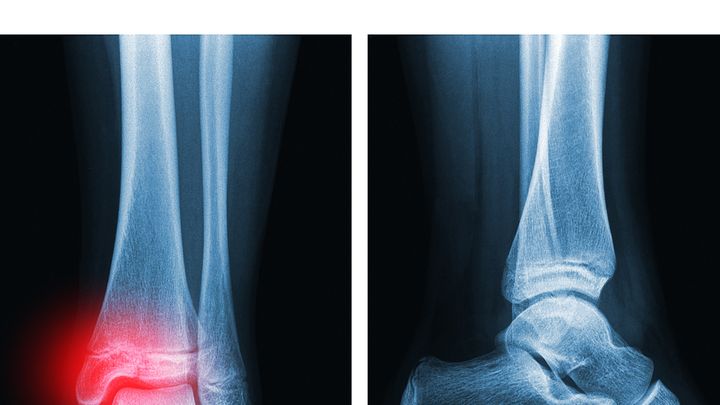

Cuando los huesos se fracturan, pueden regenerarse por sí solos si el daño es mínimo. Sin embargo, en algunos casos se necesitan implantes para favorecer la cicatrización, los cuales pueden estar hechos de metal, tejido óseo de donante o materiales impresos en 3D. Especialmente en el caso de fracturas irregulares, estos implantes deben diseñarse y fabricarse antes de la cirugía para que se ajusten al caso concreto.

La técnica se probó en conejos con fracturas graves de fémur y, al parecer, favoreció una regeneración más eficaz del tejido dañado que el cemento óseo convencional utilizado en los grupos de control. Los animales fueron monitoreados durante 12 semanas tras la intervención y no mostraron signos de infección ni necrosis, es decir, muerte del tejido circundante.